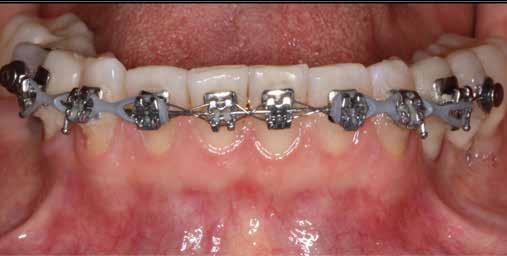

Az alignerekkel történő fogszabályzó kezelés elvégzéséhez az Invisalign rendszert használtuk. Az orthodonciai kezelés során 14 sín került felhasználásra. A páciensnek minden egyes sínt 10 napon keresztül kellett viselnie. A fogszabályzó kezelés céljai között szerepelt az élharapás megszüntetése, a szemfogak derotálása, valamint az alsó fogíven látható torlódás feloldása.

Az orthodonciai terápia során a fogív tágításra került, és a fogak között látható rések is egyenletes módon lettek elosztva a frontfogak között. Erre azért volt szükség, hogy a restauratív fázis során lehetőségünk legyen a harmonikus szé-

lességű és hosszúságú fogformák kialakítására (5. ábra)

A labiális és bukkális fogfelszínekre helyezett attachmentek feleltek a sínek által a fogakra kifejtett erők megfelelő átvitelének biztosításáért. Az eset ellátása során végzett orthodonciai előkezelést funkcionális szempontból a protetikai vagy restauratív célú fogászati beavatkozások közé sorolhatjuk. Ebben az esetben az orthodonciai beavatkozásnak az volt a célja, hogy lehetővé tegye a definitív fogpótlások minimálinvazív módon történő elkészítését. Az alignerekkel történő fogmozgatások befejezését követően a pácienst egy felső retenciós sínnel láttuk el. Az alsó fogíven az elért eredmények stabilitását fix retainer felhelyezésével biztosítottuk.